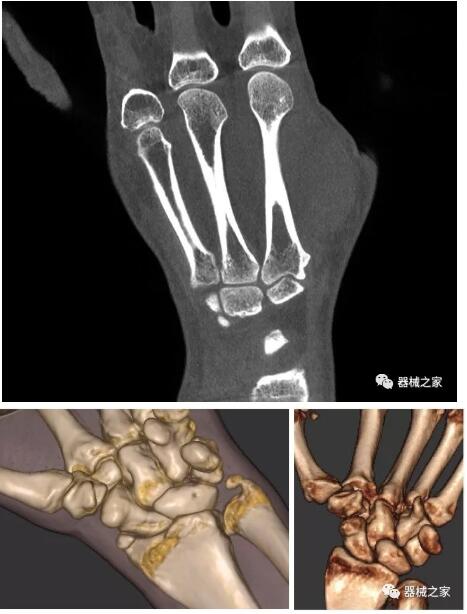

另外一款被稱為世界上最小的CT,它的重量?jī)H300磅,不僅能夠掃查足部,還可以檢查膝蓋和上肢等。

與上面介紹的CT一樣,它同樣具有輻射低、占地空間小(23*36)的特點(diǎn),隨開隨用(支持直接接入墻上的插座)。

這款CT使用非常方便,通過上下移動(dòng)保持與患者的手臂或者雙腿齊平,掃描快速,僅需要30秒左右就可以完成掃查。

以上介紹的CT均來自國(guó)外同一家公司,這些CT均配置了可視化軟件,可以進(jìn)行切片、3D重建以及大型CT附帶的所有典型的操作功能。

以下是這些“特立獨(dú)行”的CT所拍出來的圖像: